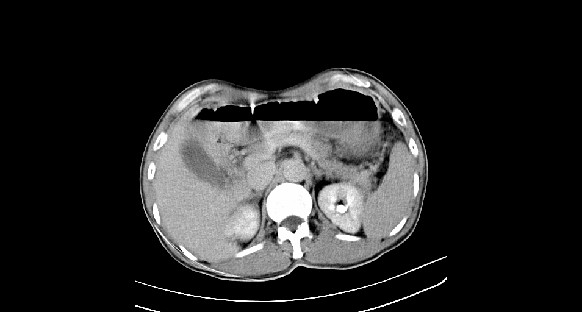

男性,70岁,体检b超发现左肾占位,请各位战友发表一下观点

左肾有两个病灶,且较大的病灶内可见点状钙化灶,增强扫描边缘也是呈渐进性强化,中央部分未见明显强化